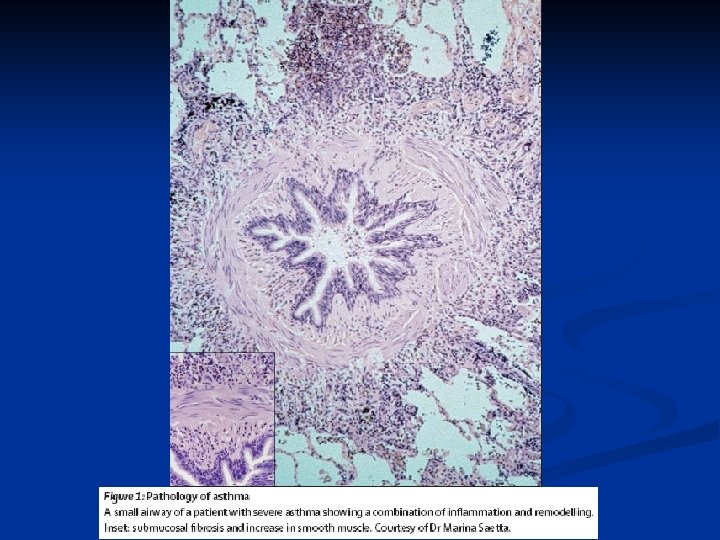

Small airway wall thickening in asthma Chronic Severe Acute Fatal Normal

Remodelación vía aérea Cambios estructurales: incremento del músculo liso, hiperplasia de las glándulas mucosas, angiogénesis y depósito colágeno en la sub membrana.